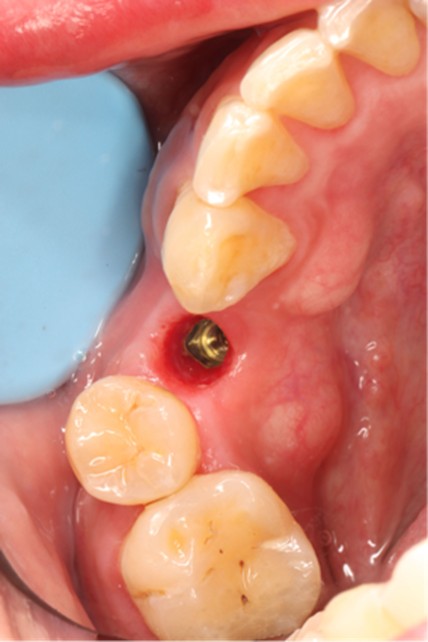

December 4, 2025: Definitive crown delivery. The margin of the implant-supported crown exhibited optimal adaptation.